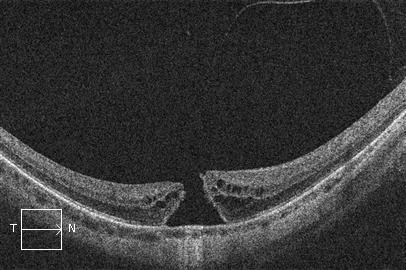

El procedimiento quirúrgico del agujero macular es la vitrectomía que consiste en retirar el humor vítreo para trabajar sobre la retina. Se realiza entonces un pelado de una fina capa de la retina (membrana limitante interna) y se introduce un gas dentro del ojo que contribuye en el cierre del agujero macular. Es una intervención no dolorosa que se hace bajo anestesia local (retrobulbar) y de forma ambulatoria.

OCT. Agujero macular antes de cirugía